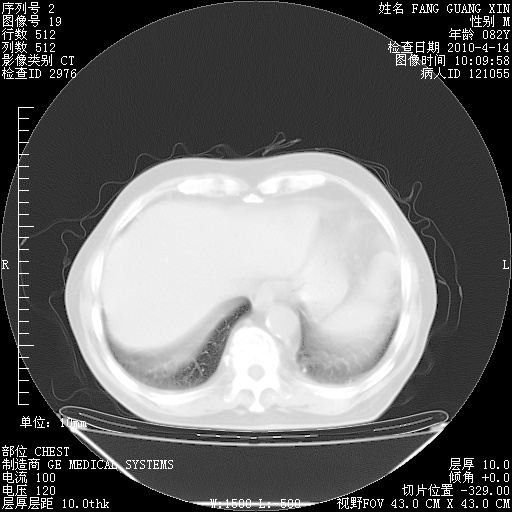

肺部CT平扫未见异常。